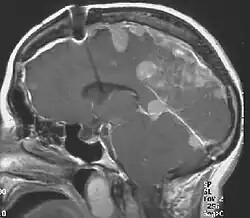

- Obustronne schwannoma nerwu przedsionkowego potwierdzone histopatologicznie lub widoczne w MRI ze wzmocnieniem kontrastowym, lub

- MRI mózgowia i rdzenia ze wzmocnieniem kontrastowym.